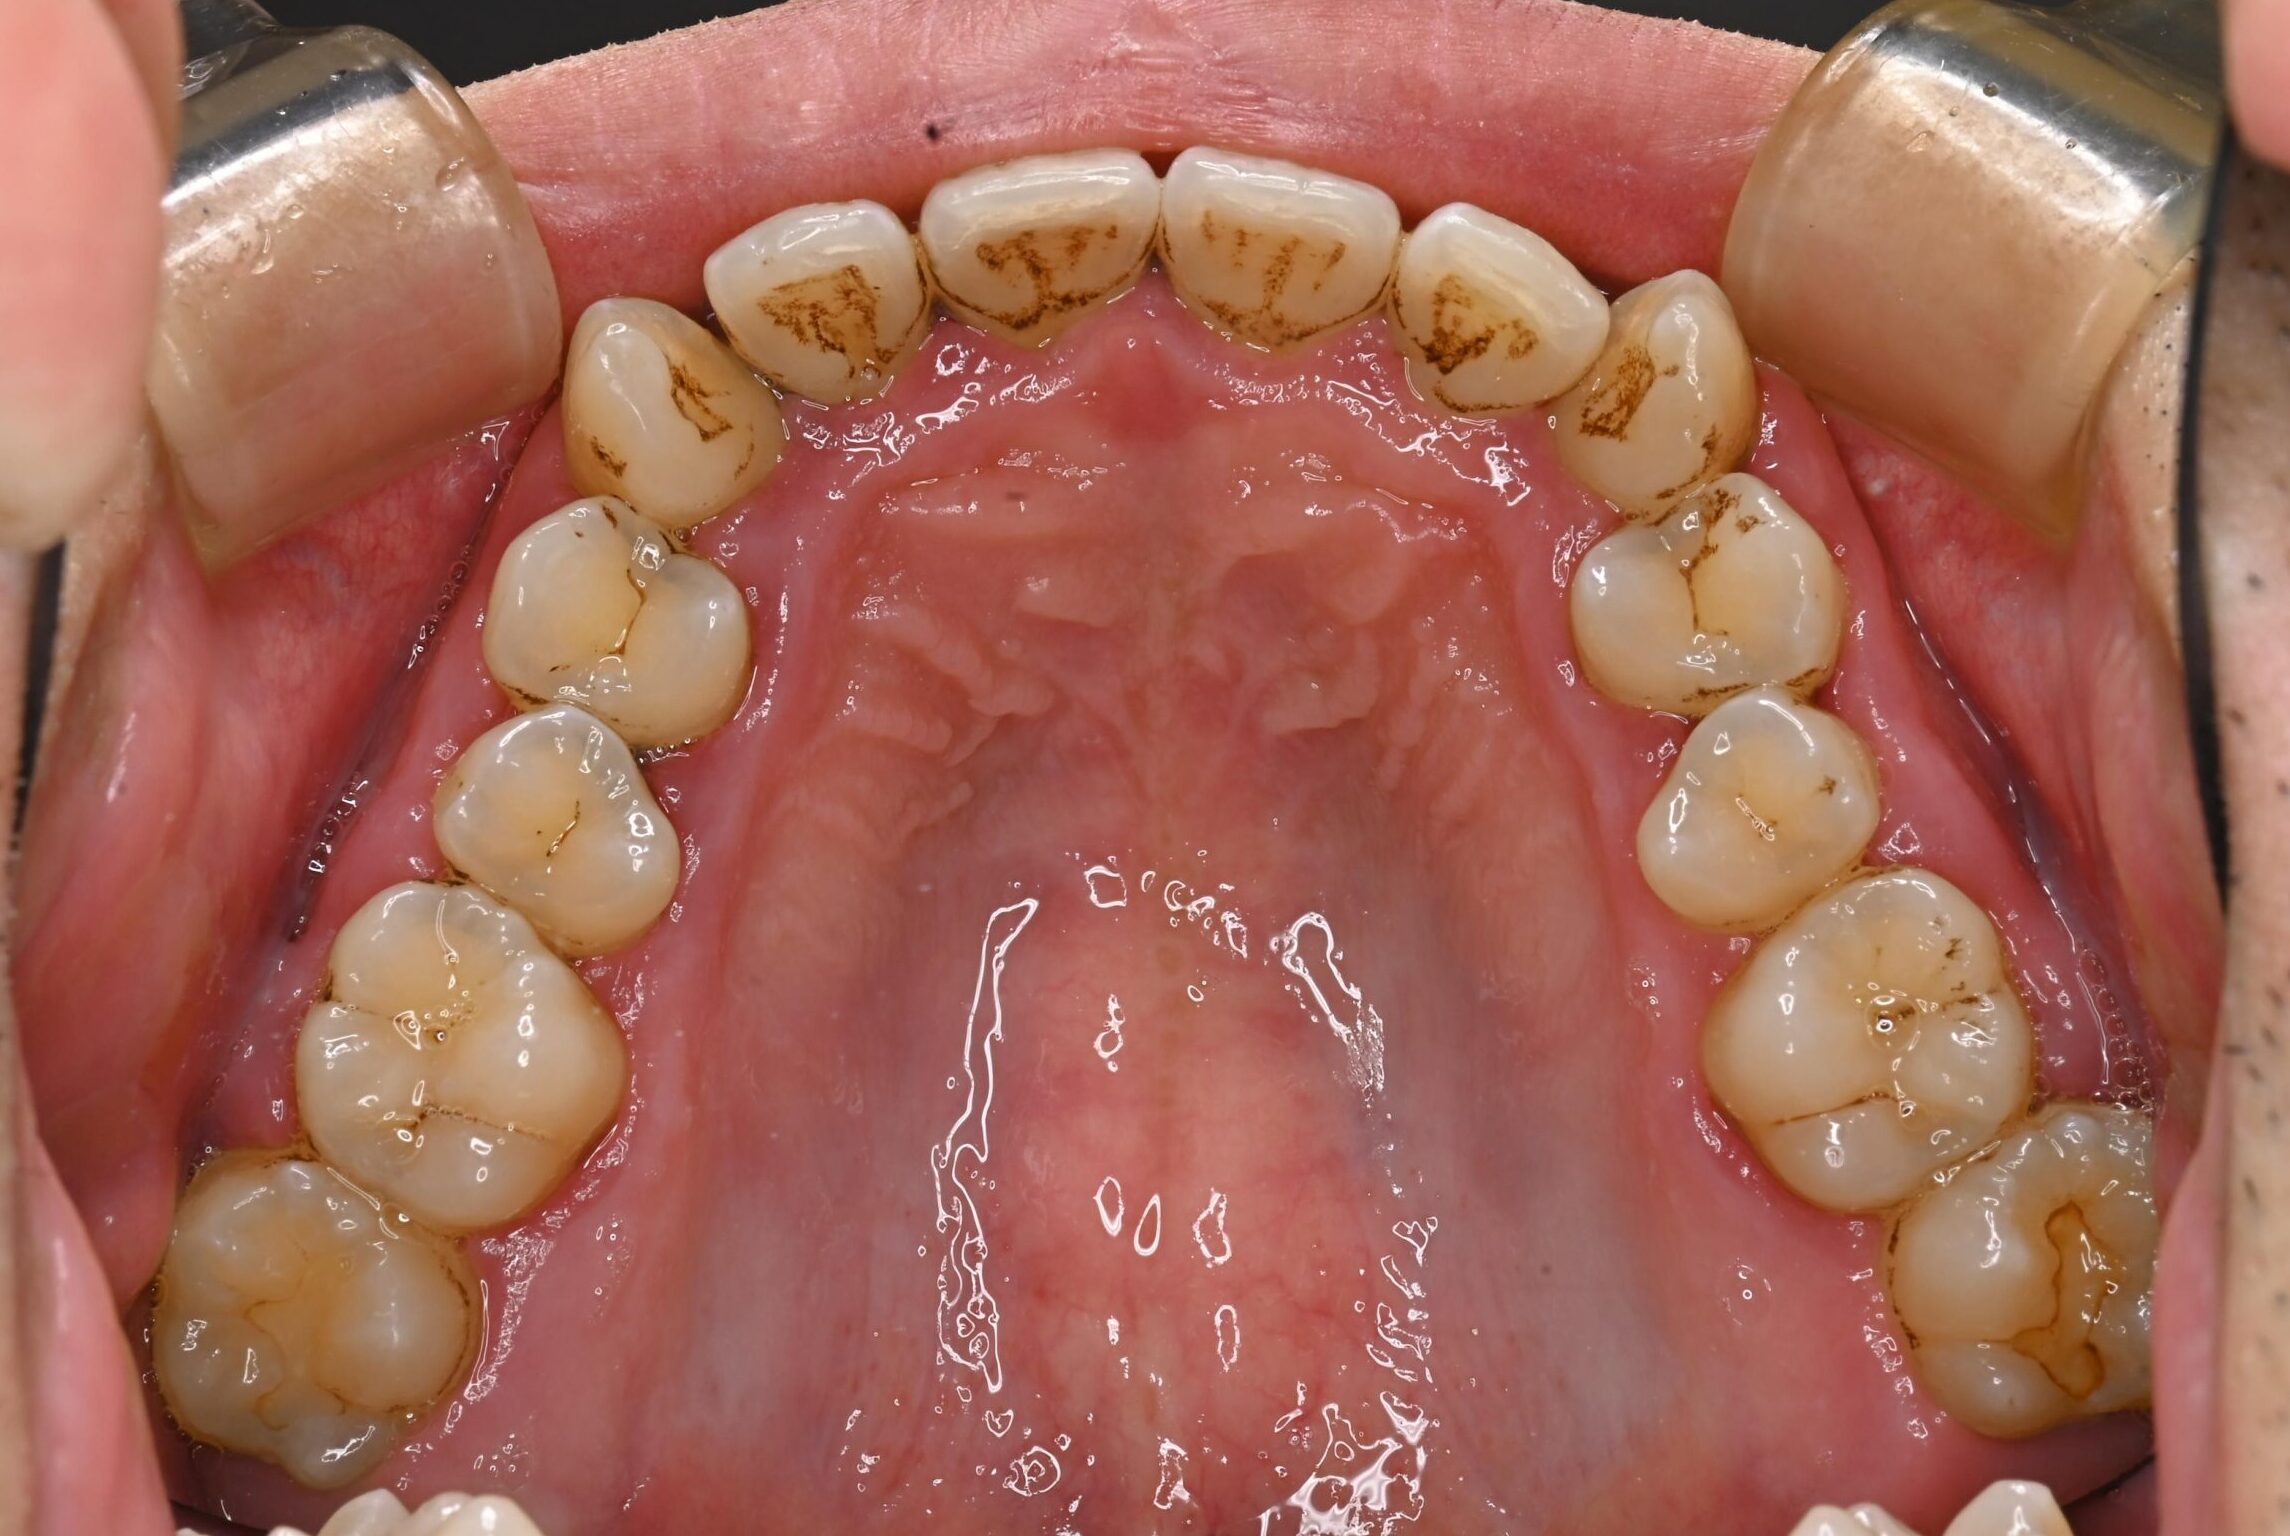

30代・男性

歯茎から出血、歯石除去|中等度に進行した歯周病

症例写真 before

中等度歯周病

歯医者が久しぶりなのでクリーニングをしてほしい、ということで来院されました。

レントゲン撮影、歯周検査などを行なった結果、全体に多くの歯石付着が認められる進行した中等度の歯周病であることが判明しました。ご本人も歯茎から出血することは気になっており、担当歯科衛生士から歯周病について説明を行いました。

今回は歯石の付着が広範囲に渡っており量も多いことから、歯科衛生士による歯周基本治療に加え歯科医師による外科手術も行うことで、徹底的に治療していくことになりました。